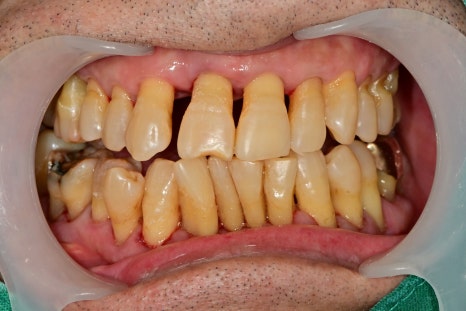

전반적으로 스케일링과 치주치료를 진행한 후 사진입니다.

이미 내려앉은 잇몸은 다시 채울 순 없지만 더 이상의 염증의 진행을 막고

부어있던 잇몸을 가라앉혀야 임플란트나 다른 치료들이 예후성이 좋아집니다.

양쪽 어금니 모두 흔들리는 상황이지만 한쪽이라도 식사를 하셔야 하기 때문에

가장 불편한 곳 먼저 치료를 하기 시작했습니다.